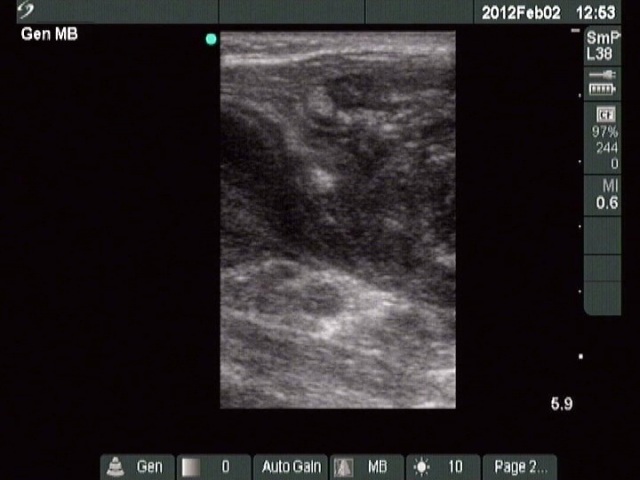

Ultrasonography: Both lobes were deeply hypoechoic. There was a large lymph node just lateral to the left thyroid lobe. The node had a central scar and presented echonormal discrete fields as well. It is worth noting that the left thyroid lobe was more inhomogeneous compared to the other thyroid lobe. This inhomogeneity made the appearance of the left lobe close to the tumorous lymph node.

On the ultrasound presentation, it was not evident that the thyroid also has malignant lesion, but the histopathology disclosed that the lymphoma was present even within the thyroid.